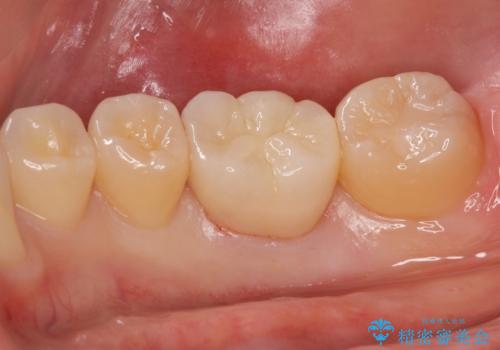

ジルコニアクラウンにて治療しました。

- ジルコニアクラウン・仮歯 12.1万円費用は治療当時の料金となります